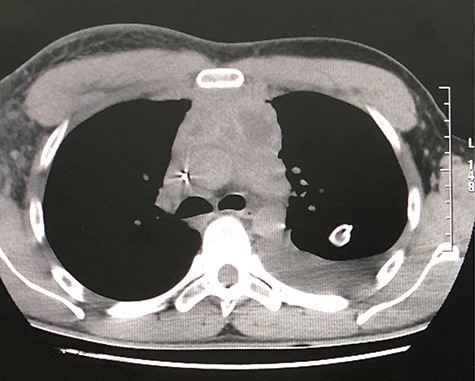

The first case consists of a 26-year-old male that presented with dyspnoea at rest, tachycardia, jugular vein distention, and slight facial and upper limb edema. The patient had been previously treated with ceftriaxone and moxifloxacin, and underwent a left thoracostomy due to a chest radiograph that showed a pleural effusion in the left inferior hemithorax. At auscultation, the patient had reduced air entry in the left lung base. The patient did not show improvement with the treatment previously given, so new laboratory tests were ordered. The blood test showed an elevated lactate dehydrogenase at 652 U/L and the pleural fluid analysis showed an elevated lactate dehydrogenase at 911 U/L, cholesterol level at 46 mg/dl, and triglyceride level at 847 mg/dl. According to these results, the pleural effusion was classified as an exudate. The high triglyceride level was consistent with a chylous effusion. A chest CT confirmed a pericardial effusion, the previously noticed free pleural effusion, and an irregular mass in the anterior mediastinum with heterogeneous density that included hypodense areas that suggest necrosis (Figs 1 and 2). Subsequently, the patient underwent surgical treatment, which consisted of a pericardial window. Aside from this procedure, the anterior mass was biopsied. Histological analysis revealed a non-Hodgkin lymphoma. Due to the diagnosis, the patient was transferred to the hematology care unit to receive chemotherapy, but he continued to deteriorate and passed away 2 months later.

CT scan axial view of anterior mediastinal mass, left lung free pleural effusion and intercostal drainage.